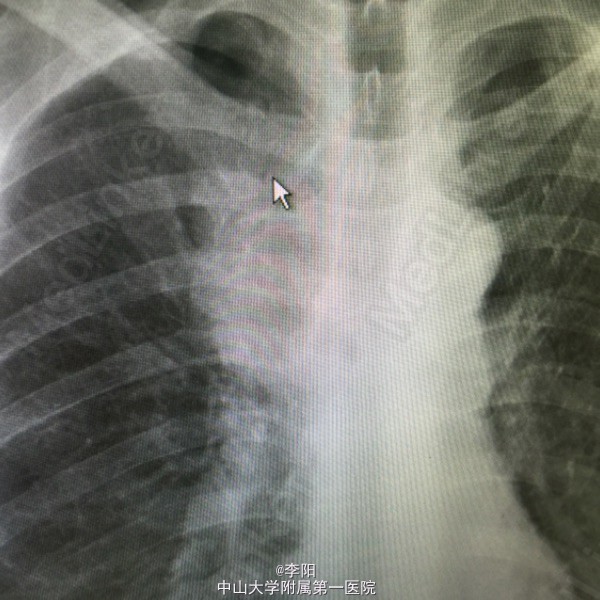

右前上纵隔肿块

患者三月前无明显诱因反复出现夜间胸骨中上段后方闷涨感,mr示右前上纵隔旁肿块,考虑纵隔旁肺癌。